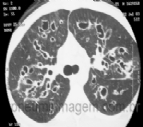

DIRETRIZES BRASILEIRAS DE DIAGNÓSTICO E TRATAMENTO DA FIBROSE CÍSTICA: FAÇA O DOWNLOAD

A fibrose cística (FC) é uma doença genética autossômica recessiva caracterizada pela disfunção do gene CFTR. Trata-se de uma doença multissistêmica que ocorre mais frequentemente em populações descendentes de caucasianos. Nas últimas décad...